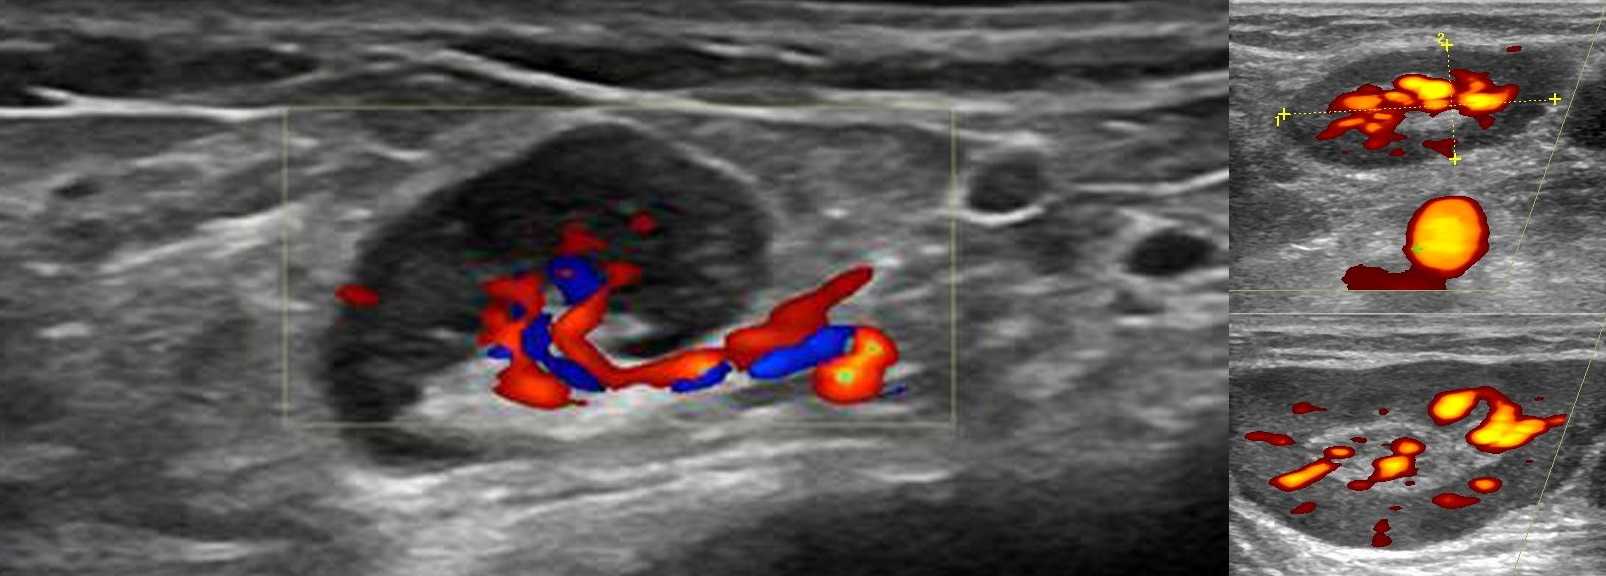

Подмышечная лимфаденопатия сопровождает целый ряд заболеваний молочных желез: фиброзно-кистозную, диффузно-узловую мастопатию, фиброму, липому, рак груди. УЗИ позволяет наилучшим образом оценить дифференцировку корковой и центральной частей узлов, выбрать узел для биопсии. Чаще всего пользуются УЗИ с цветным картированием. Возможна эластография, оценивающая плотность разных участков лимфатического узла.

Лимфатические узлы здорового человека – это гипоэхогенные образования, имеющие овальную форму с более плотной центральной частью, длину не больше 15 мм, соотношение их длины и толщины составляет не меньше 20 мм. В организме лимфоузлы расположены группами, их количество у разных людей может значительно отличаться. В структуре узлов выделяют участки – так называемые «ворота», в которые входят кровеносные и лимфатические сосуды. Оценить их состояние, ток крови и лимфы возможно с помощью метода прямой визуализации – цветового допплеровского картирования (ЦДК).

При наличии у пациента лимфаденита наблюдается равномерное увеличение узлов и повышенная васкуляризация (увеличение общего числа сосудов), однако их структура не изменена. Метастатическое поражение приводит к округлению узлов и деформации сосудов.